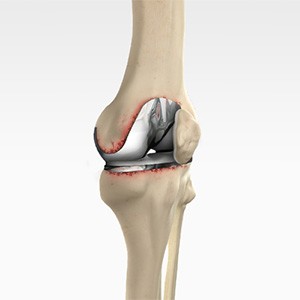

Revision Knee Replacement

Revision knee replacement surgery involves replacing a part or all your previous knee prosthesis with a new prosthesis. Although total knee replacement surgery is successful, sometimes the procedure can fail due to various reasons and may require a second revision surgery.